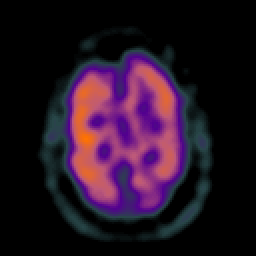

Subacute Stroke overlay -- Slice #18

[Home][Help][Clinical] Slice 18